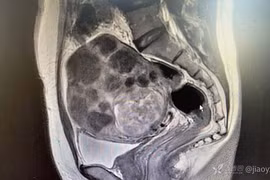

(VietnamDaily) - Phát hiện u xơ tử cung cách đây 5 năm, bệnh nhân 42 tuổi không hề điều trị. Chủ quan suốt thời gian dài đến khi bụng to bất thường, người phụ nữ đi khám rồi ngỡ ngàng phát hiện tử cung “mọc” u chi chít như sung.